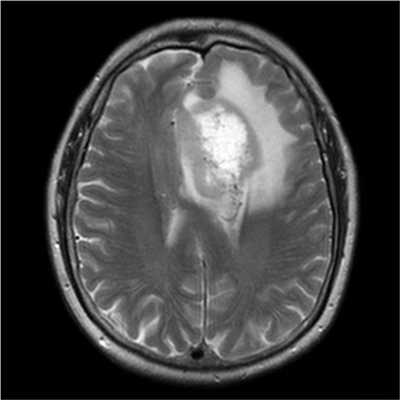

- перифокальный отек в виде размытого ореола вокруг очагового образования, зоны некроза (омертвения)

На снимках метастазы выглядят, как очаговые неоднородные образования, единичные или множественные, с тенденцией к слиянию, может присутствовать зона некротизации. Пораженный лимфатический узел чаще округлой формы, увеличен в размерах. Для лучшей визуализации используют контрастное вещество на основе солей гадолиния.

Злокачественные опухоли характеризуются инвазивностью, то есть врастанием в здоровые ткани, поэтому контуры таких образований нечеткие и неровные, а потому достоверно определять границы таких опухолей довольно сложно. Кроме того, структура злокачественной опухоли часто бывает неоднородна за счет распада (некроза), кровоизлияния и коллоидной дегенерации. Вокруг злокачественной опухоли, как правило, выявляется выраженный перифокальный отек, который может приводить к смещению срединных структур головного мозга и появлению аксиальной дислокации. Также могут быть выявлены признаки метастазирования.